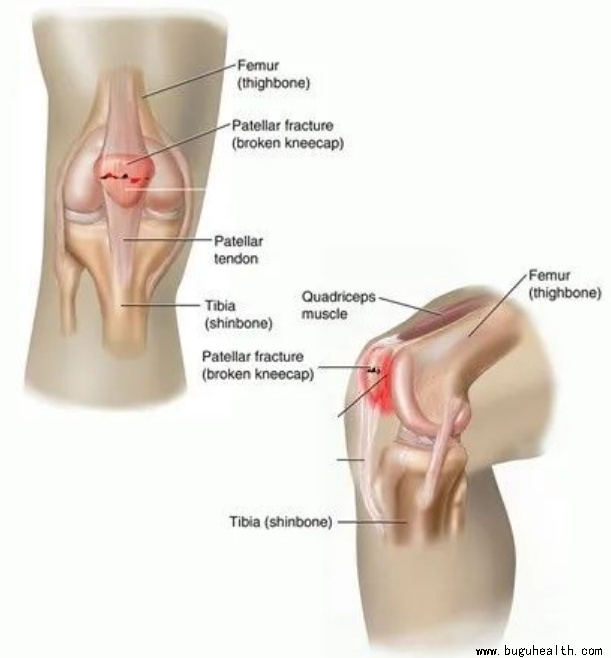

4. 髌骨骨折

属于膝盖骨折,髌骨是膝关节的重要组成部分,髌骨骨折后常发生膝关节肿胀积血,髌前可见皮肤擦伤及皮下血肿,压痛明显,有移位的骨折可触及骨折间隙。

未移位骨折或移位不太明显可保守治疗

保守治疗主要是指:

①固定,石膏或支具固定根据医生的建议时间复诊,如果最终稳定,可佩戴石膏或支具直到伤后4~6周拆除石膏,直到骨痂更可靠。

②积极康复训练,包括膝盖的主动及被动活动,以及渐进式恢复运动强度,避免髌骨顽固粘连。